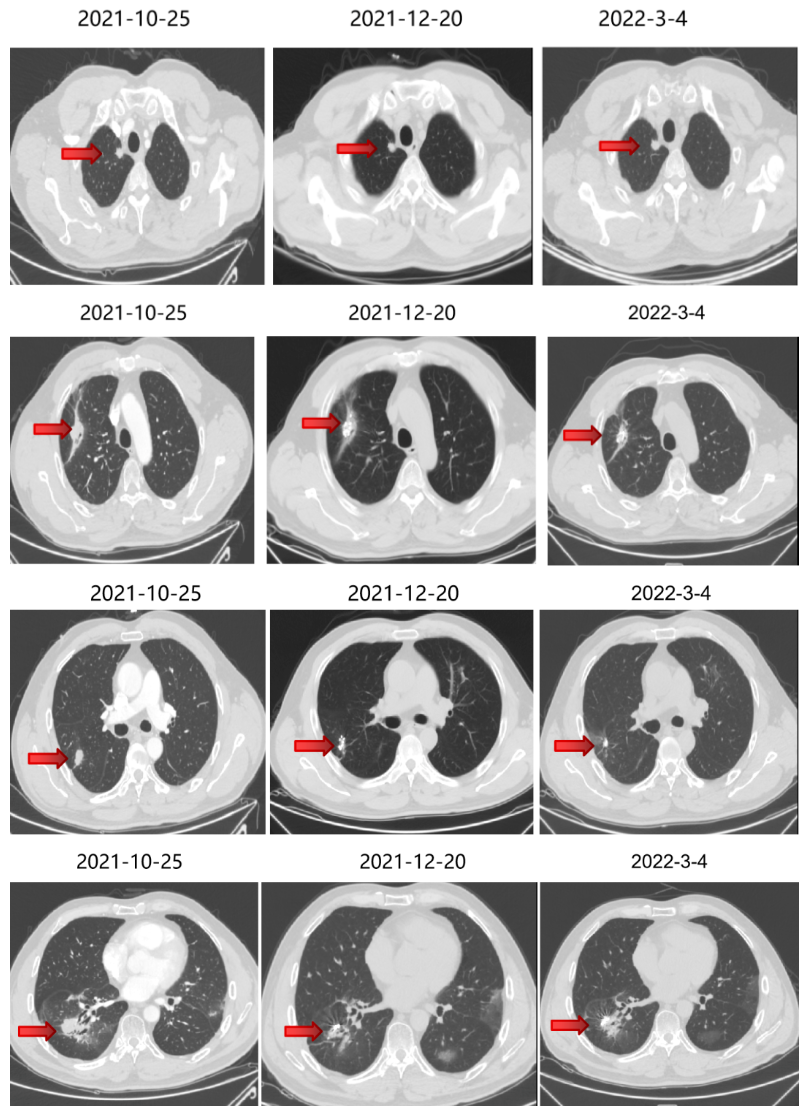

局部治疗(二):SBRT治疗

2020-11-6至2020-11-25 左肺下叶及右肺下叶转移灶放疗:95% PTV1-2 74.7Gy/4.98Gy/15F。

2020-12-31至2021-1-19右肺上叶转移灶放疗:95% PTV 74.7Gy/4.98Gy/15F。

SBRT疗效评价:部分缩小。

期间2021-3-15胸部CT:双肺转移瘤部分较前略增大,疗效SD。

三线治疗疗效评价:部分增大,PD。

2021-6-17 起口服曲氟尿苷替匹嘧啶片(TAS-102)40mg bid。

四线治疗疗效:部分略减小,SD。

2021-10-29、2021-11-1 行CT引导下双肺转移灶放射性碘125粒子植入术。

继续曲氟尿苷替匹嘧啶片(TAS-102)40mg bid+瑞戈非尼40mg qd(2021-11始)至今。

五线治疗疗效:病灶控制良好。

2022-4-13、2022-4-15 行CT引导下双肺转移灶放射性碘125粒子植入术。